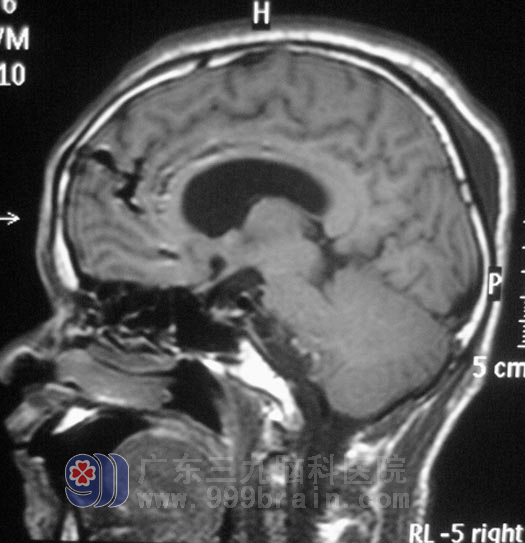

区先生,今年44岁。五年前开始出现右耳听力下降,间断头晕,呈阵发性,当地医院考虑是五官科问题,予对症治疗后症状无明显好转,且右耳听力下降不断加重。三个月前,他逐渐出现双眼视力下降,间断头晕伴有恶心感。头颅CT检查,结果提示“右侧桥小脑角区占位,约3.5cm×3.2cm,考虑听神经瘤,伴梗阻性脑积水”。

入住广东三九脑科医院综合神经外科时,区先生左侧侧鼻唇沟变浅,露齿时口角向右侧歪斜,双耳听力下降(右耳明显),闭目难立征(+),易向右侧倾倒。12月20日,由鲁明主任主刀,在全麻下行右侧乙状窦入路听神经瘤切除术。术中显微镜下见黄白色肿瘤组织,位于右侧桥小脑角区,质软,血供丰富,面神经位于肿瘤前下方,副神经、迷走神经、舌咽神经位于肿瘤后下方,神经组织形态菲薄,在显微镜下用超声刀分块切除,磨钻磨除部分内听道,切除内听道内肿瘤组织,中后组颅神经保护完好,手术顺利结束。术后病理结果为:(右侧桥小脑角)神经鞘瘤。